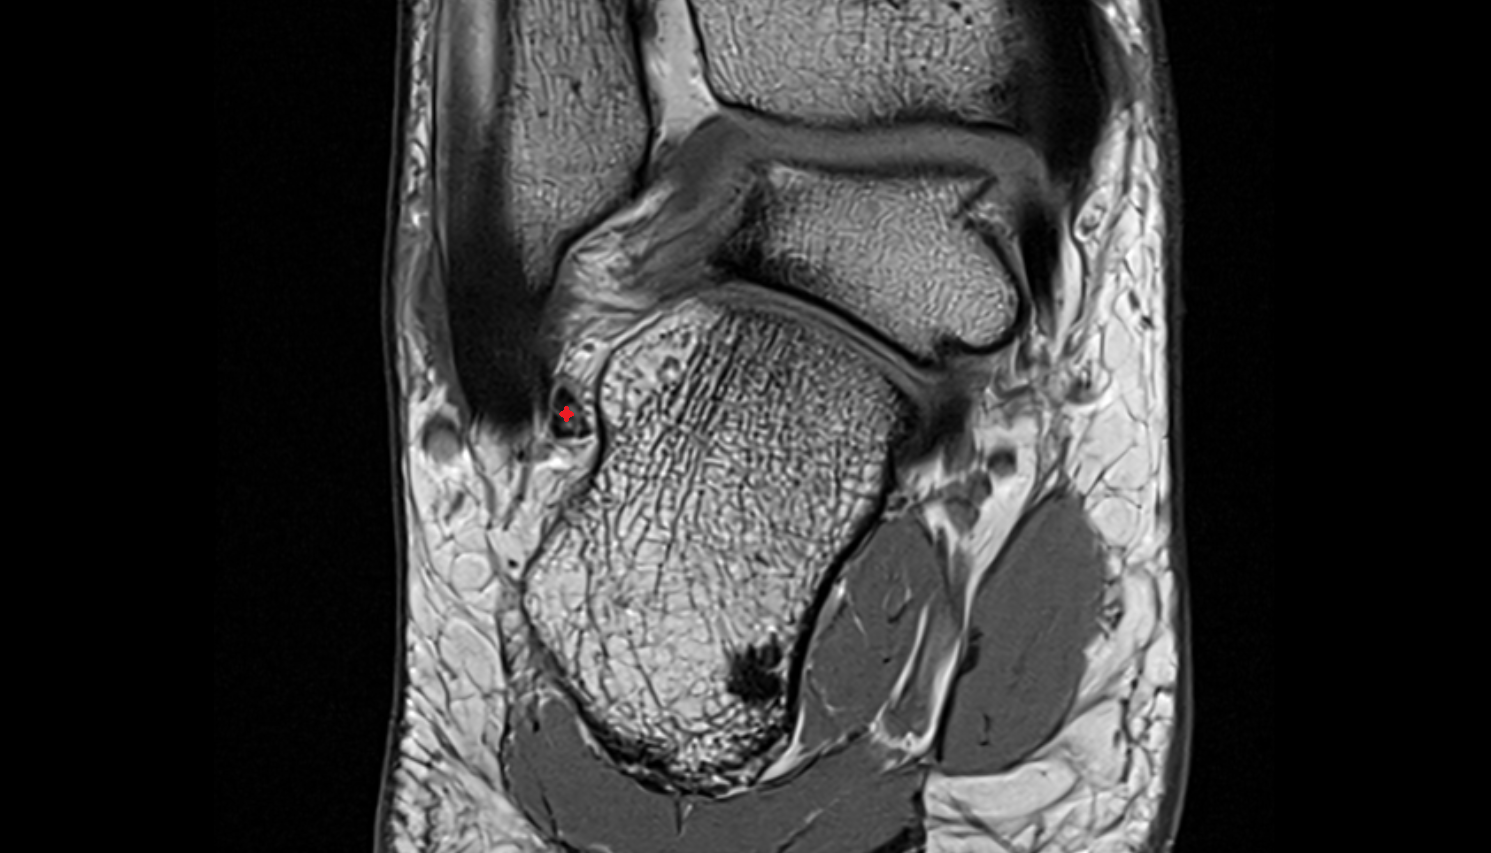

- Obturator artery

- Hip joint